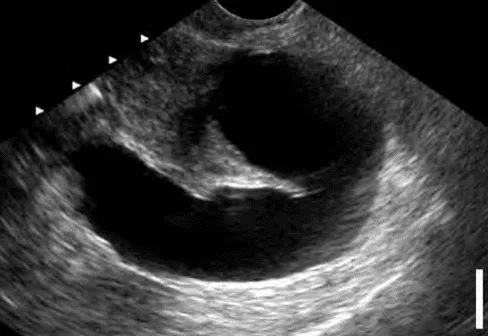

Siêu âm: ứ dịch vòi hình ảnh dãn, chứa dịch - thường hai bên.

Hình ảnh “Vòi Fallope ứ dịch trên siêu âm”.

Bệnh học: Viêm mạn tính khiến vòi xơ hóa, bít tắc, dễ tạo ổ viêm thứ phát đa vi khuẩn (kể cả kỵ khí). Nội độc tố, cytokine, gốc tự do từ ổ viêm lan vào buồng tử cung. Môi trường dịch vòi nghèo dinh dưỡng, đặc biệt ít glucose. Ứ dịch vòi sau Chlamydia có thể giảm hiệu quả làm tổ trong IVF. Cắt bỏ vòi ứ dịch trước IVF cải thiện tỉ lệ làm tổ. Dịch vòi tổn thương chứa độc tố, ảnh hưởng sản xuất cytokine (IL-1, LIF, CSF-1, integrin αvβ3) làm tổ.